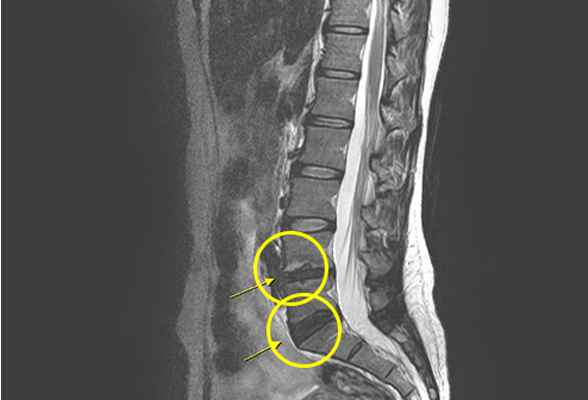

척추전방전위증

척추전방전위증은 척추뼈가 분리되어, 분리된 부분의 위쪽 뼈가

앞쪽으로 밀려 나가 통증을 일으키는 척추질환을 말합니다.

척추뼈가 분리된 척추분리증이 오랜 기간 지속 되었을 때 척추 전방전위증이 발생할 수 있습니다.

비수술 치료 : 약물치료, 도수치료, 신경차단주사, 경막 외 신경성형술, 풍선확장 신경성형술

수술치료 : 최소침습 척추유합술